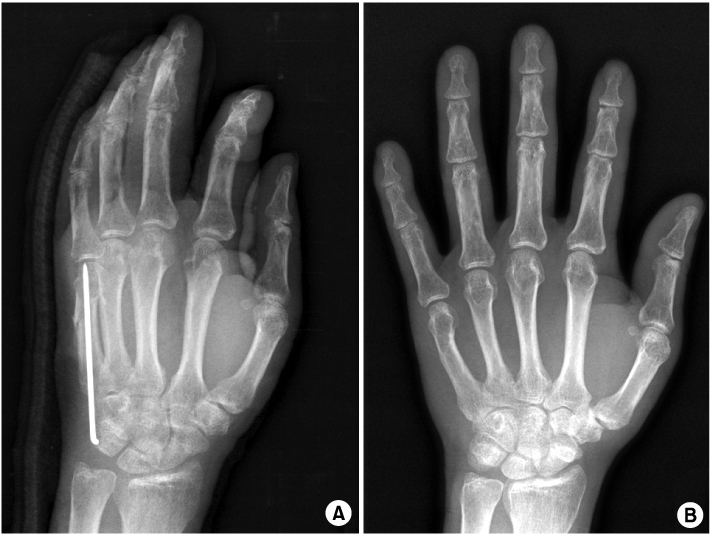

Fig. 5

Pin was migrated to the metacarpophalangeal joint in postoperative 4 weeks (A). After 6 months, complete bone healing occurred without loss of reduction (B).

The average follow-up period was one year nine months, with a range of 12~42 months. Average operation time was 18 minutes (range, 12~27 min) and no immediate complication was seen. Rotational malalignments were detected in 4 cases preoperatively and they were corrected by manual reduction without any further invasive procedure. Distal migrations of K-wire tip to the MP joint were seen in two patients during the follow up. One patient showed migration in postoperative 3 weeks and the other in 4 weeks (Fig. 5). Migrated pins were removed immediately at the time of detection and gentle ROM exercise was recommended within the splint.

Radiological evaluation revealed evidence of callus formation in all fractures at 41 days in average (range, 34~58 days) such that splints and wires were removed at the same time in out-patient clinic. All the fractures had united and mean angular deformity were 3° (0~7°) in the coronal plane and 1.2° (0~5°) in the sagittal plane. Previous penetrated metacarpal heads by K-wire were healed completely without any residual change on the last follow up x-ray and there was no measurable shortening. At the final follow up, all patients had regained little finger MP joint motion of average extension 9°, flexion 87°. None of the patients had other joints stiffness at the final follow up. By TAM grading system, it ranged from 225° to 260°, mean was 253°. All patients stated subjectively that the function at the MP joint of little finger had returned to normal including the patient who had pin migration. DASH score was average 2.6 at the last follow up, ranging from 0 to 8. None of the patient had a clinically detectable rotational deformity and they reported satisfaction with their resulting appearance. Even though small skin incision was made during pin removal, it did not make any remarkable scar. Mean cosmesis score was 1.6 and it indicated the appearance was better than virtually normal. All continued with their previous occupations.